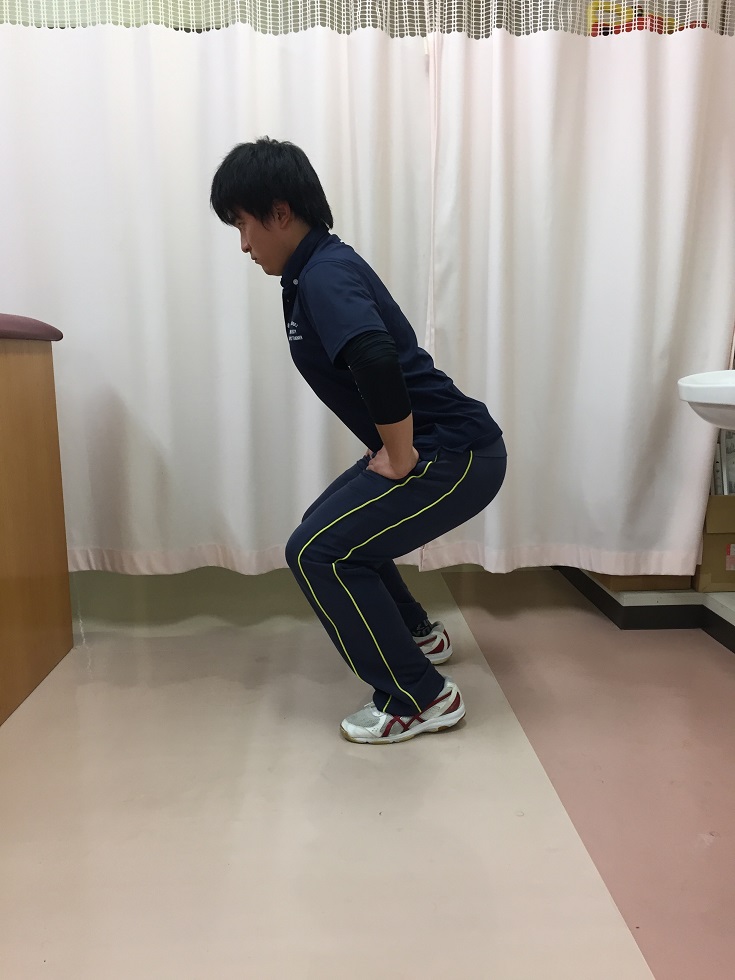

ハーキー

導入としてハーキー(脚をその場で速く小刻みに踏む)を行います。ハーキーは左右の足の間隔(スタンス)が広くなり過ぎないように注意します。 股関節と膝関節を曲げて重心が後方に傾かないように低い姿勢を心がけます。

動作中は踵をあげ(母趾球に荷重して)股関節と膝関節を曲げて低い姿勢を心がける

上半身が起き上がってしまう悪い姿勢の例